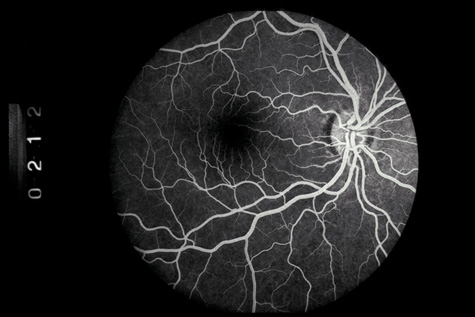

CHOROIDAL INJURIES

Posterior choroidal ruptures are probably caused by anterior-posterior compression and equatorial expansion. The retina is relatively elastic, and the sclera is relatively tough. Both resist ruptures. Bruch's membrane, on the other hand, is inelastic and more prone to rupture. The overlying RPE and underlying choriocapillaris are also torn, but in most cases, the deep choroidal blood vessels remain intact (Fig. 19). Rupture of the choriocapillaris often results in subretinal hemorrhage. Patients with angioid streaks and other conditions known to be associated with a inelastic and fragile Bruch's membrane are especially vulnerable to choroidal rupture (Fig. 20).

Initially, a choroidal rupture may be obscured by a subretinal hemorrhage caused by tearing of the choriocapillaris. Later, after the blood has resorbed, a white curvilinear streak concentric to the optic disc is seen. Only rarely is a rupture oriented radially with respect to the optic disk. Most are temporal to the disc and single, although nasal and multiple ruptures can also occur (Fig. 21).

If the choroidal rupture is under the foveola or if an associated subretinal hemorrhage extends under the foveola, the visual prognosis is generally poor (Fig. 22); however, a recent study showed that even patients with foveal or multiple choroidal ruptures can regain good central vision after extended follow-up.86 If the rupture is elsewhere the prognosis is good because the overlying nerve fiber layer is almost never torn. Therefore, a rupture can be located between the disc and the macula and yet not affect the visual acuity (Fig. 21).